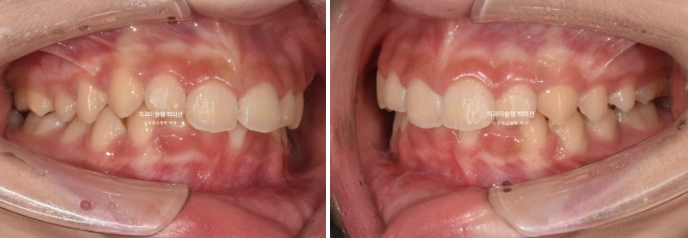

24.09

첫 세트 장치는 26개가 나왔고 고무줄 처방이 함께 들어갔습니다.

장치 26개면 모더레이트 프로그램으로 가능하다는 이야기 입니다.

24년 2월부터 9월까지 장치를 모두 낀 후 모습입니다.

중심선이 아직 맞지는 않지만 과개교합이 해소가 되었습니다.

어금니 교합이 아직 완벽하진 않습니다.

배열은 좋습니다.

중심선, 교합 개선을 위해 추가장치 제작에 들어갔습니다